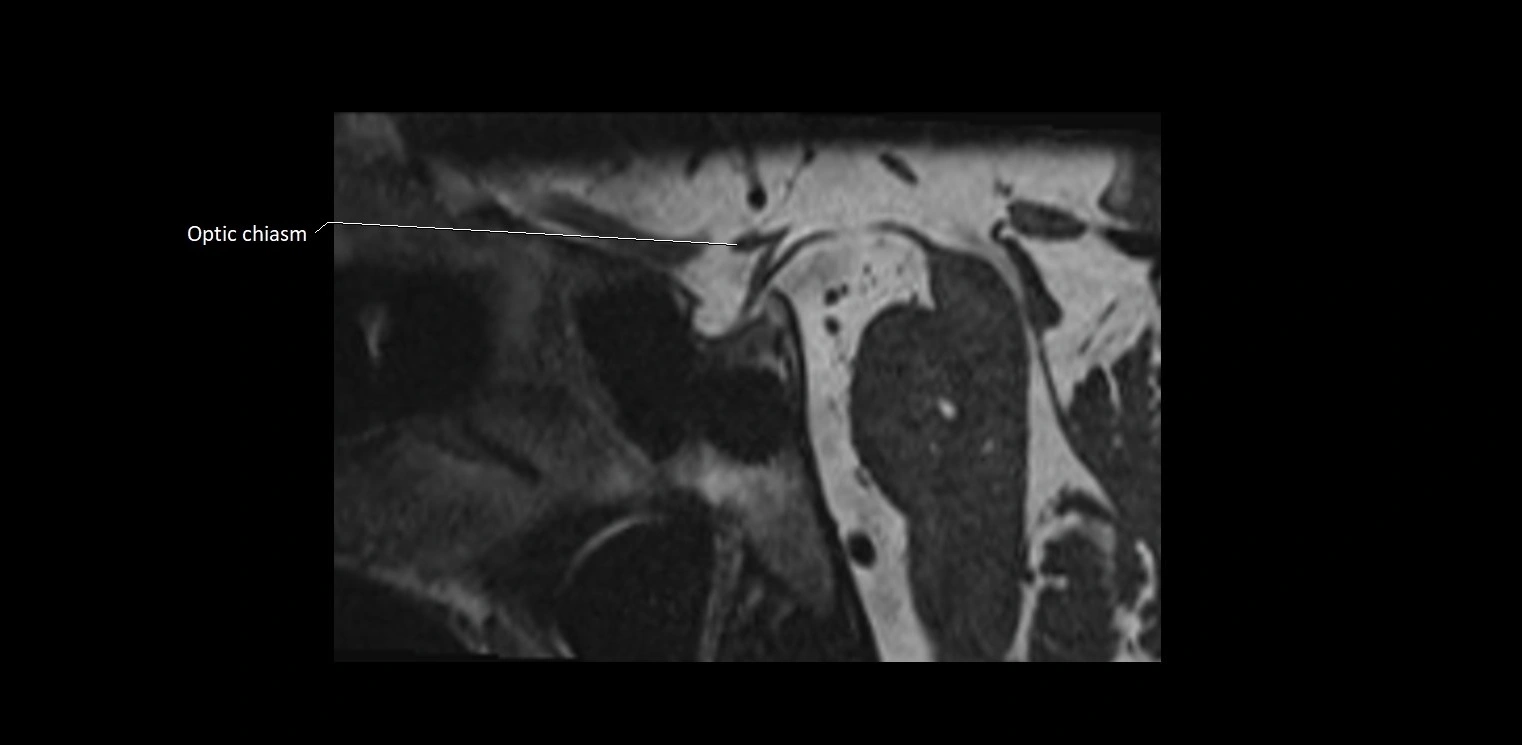

MRI Appearance

• The abducens nerve is a small, thin, linear structure

• Best visualized on high-resolution T2-weighted 3D MRI sequences (e.g., FIESTA or CISS)

• Seen as a hypointense (dark) line running from the brainstem at the pontomedullary junction, traversing the prepontine cistern, and entering Dorello’s canal under the petrosphenoidal ligament, then into the cavernous sinus, and finally the orbit

• May be challenging to visualize in standard MRI due to its small size

• Pathology may be inferred by absence, displacement, or enhancement of the nerve

MRI images

image